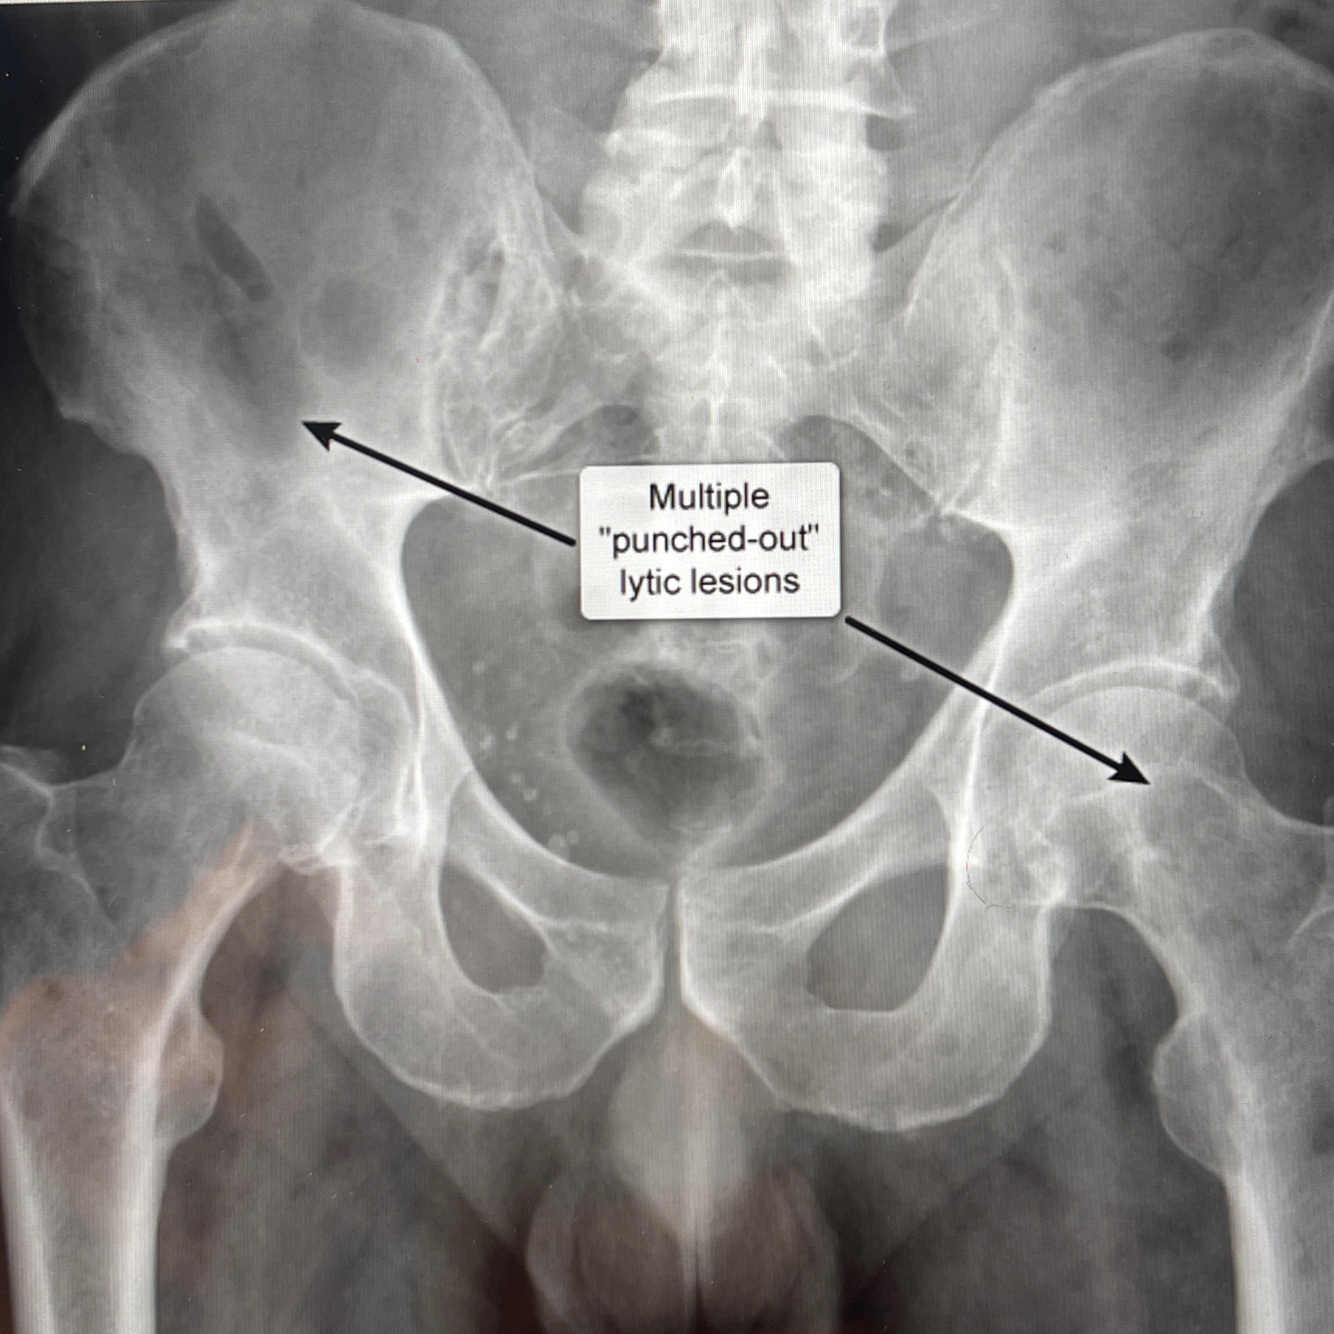

Q

A

How well did you know this?